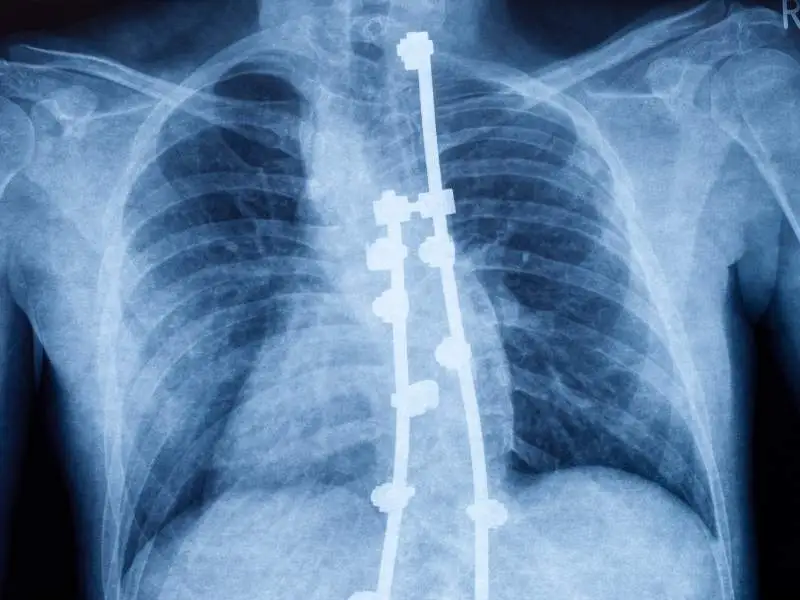

Tratamento cirúrgico da escoliose idiopática

Raio x de uma coluna vertebral com escoliose idiopática operada.

A cirurgia é indicada em casos mais graves, quando a curvatura ultrapassa os 50 graus ou compromete funções respiratórias, causa dor intensa ou afeta significativamente a estética corporal. O procedimento utiliza hastes e parafusos para corrigir e estabilizar a coluna.

De acordo com o estudo, pacientes operados apresentam melhor correção radiográfica da curva e resultados mais estáveis ao longo de 10 anos. Apesar de alguma perda parcial da correção com o tempo, os resultados permanecem duradouros e a qualidade de vida é comparável à dos pacientes tratados de forma conservadora.